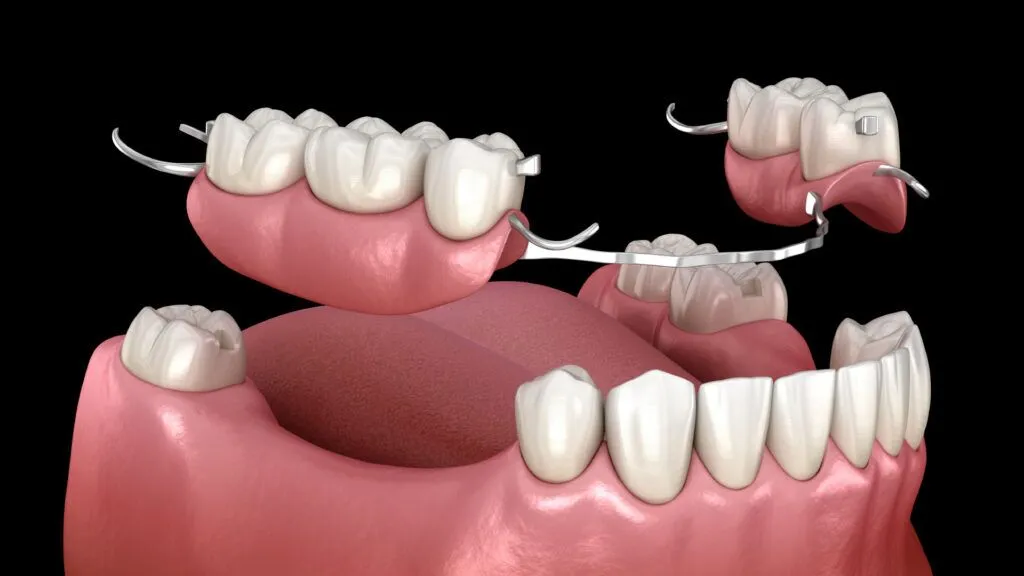

Fabrication et pose de prothèses dentaires fixes et amovibles. Couronnes, bridges et dentiers pour remplacer les dents manquantes.